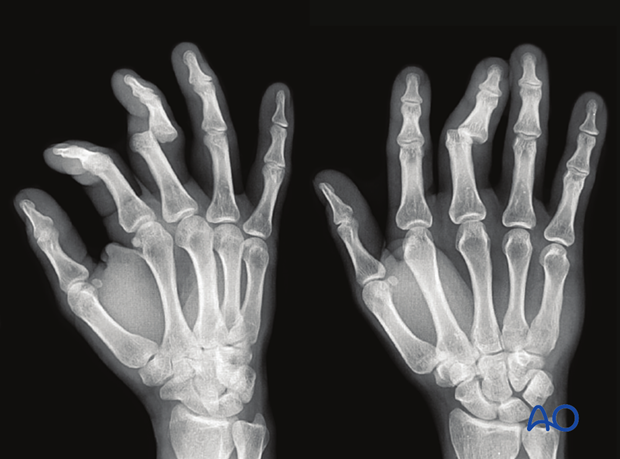

In the lateral view, the dorsal cortical profiles of the proximal and middle phalanges should be collinear. Any axial malalignment is a clear indication of subluxation.

Another indication of subluxation is the presence of a so-called V-sign in the lateral x-ray.

Oblique and AP x-rays should be taken.